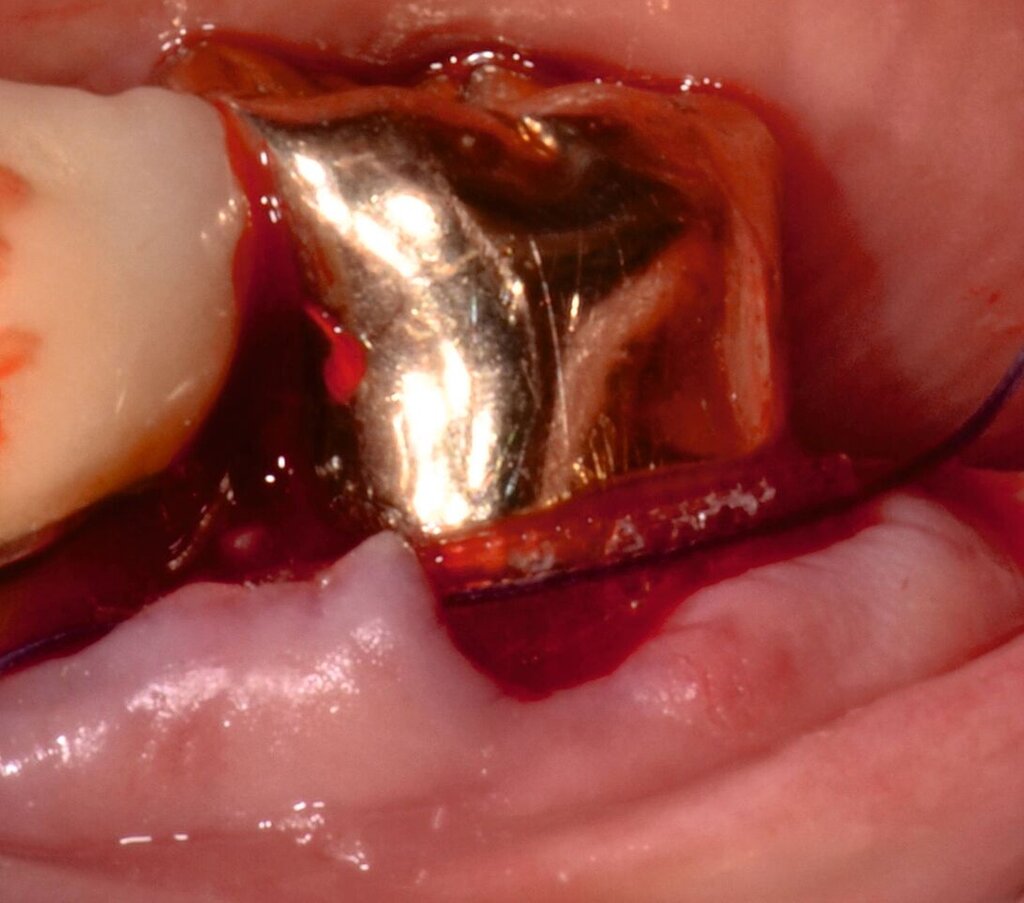

Fall 2 – fortgeschritten